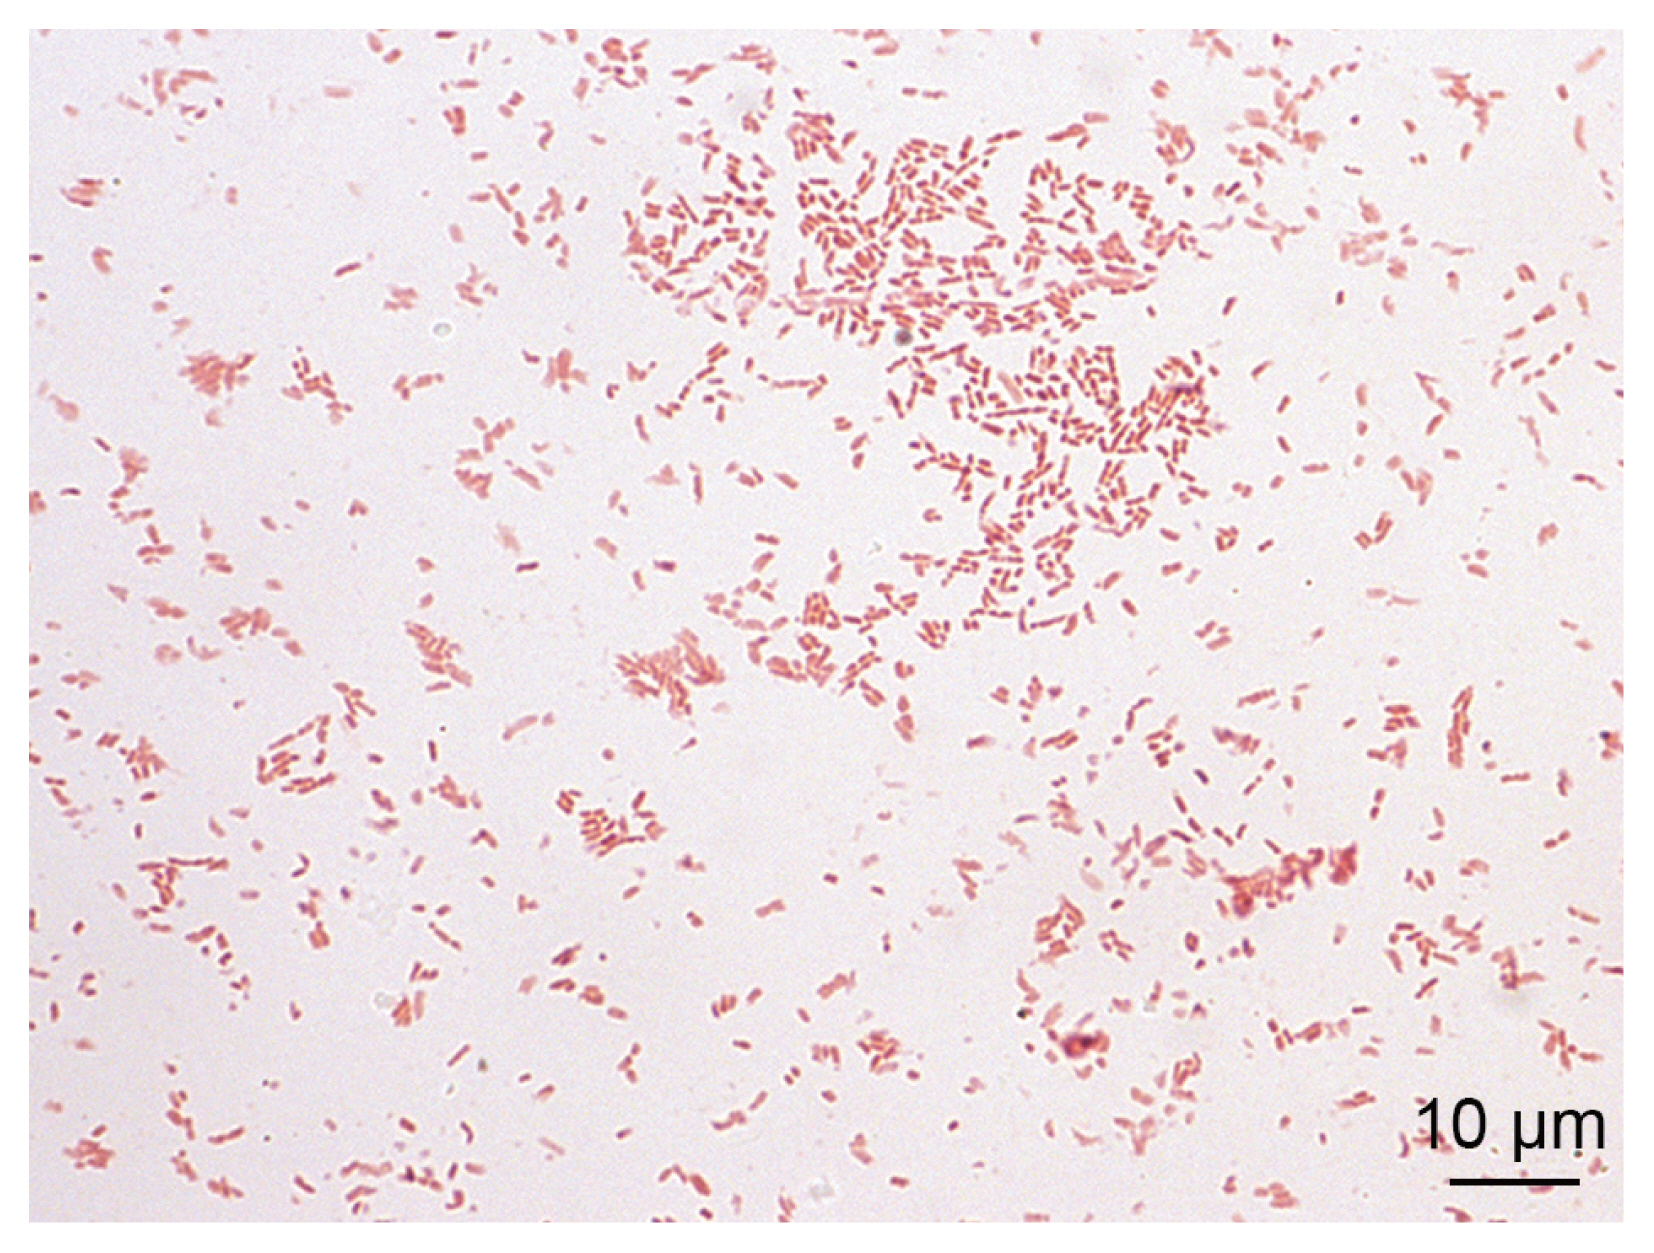

The blood cultures drawn on admission were sterile. However, of the 2 blood culture sets drawn after the second wound debridement, one anaerobic bottle was reported positive by the BD BACTEC FX blood culture system (Becton Dickinson), and Gram staining revealed Gram-negative rods (

Fig. 2). Identification of bacteria directly from positive blood culture using matrix-assisted laser desorption/ionization time-of-flight mass spectrometry (MALDI-TOF MS) (Bruker Daltonics, Server version 4.1.70 (PYTH) 48 2016-10-26_15-05-35, Billerica, Massachusetts, USA) [

Fig. 2

Ignatzschineria larvae from pure bacterial culture: Gram stain.